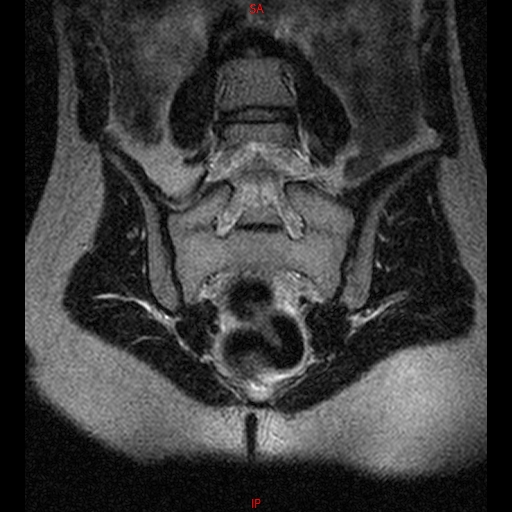

• Resonancia NORMAL SACROILIACAS COR T2

• Resonancia NORMAL SACROILIACAS  AXIAL T1